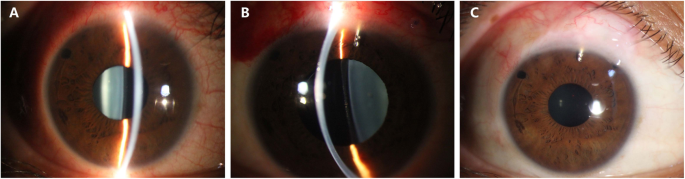

Slit-lamp photographs of the right eye. a The well-placed ICL and patent peripheral iridotomy on presentation. b The slightly shallow anterior chamber with the presence of ICL and Ex-PRESS shunt on postoperative day 1. The ICL appeared to tilt towards the cornea, and the pupil was dilated. c The well-placed Ex-PRESS shunt with a diffuse and avascular bleb 3 months after surgery

On presentation, the best corrected visual acuity (BCVA) was 20/50 in the right eye and 20/40 in the left eye. IOP was 37.3 mmHg in the right eye and 15.2 mmHg in the left eye (CT-80, Topcon Corp., Tokyo, Japan). On slit-lamp examination, the presence of well-placed ICLs without a central hole and patent peripheral iridotomies were noted in both eyes (Fig. 1a). The crystalline lenses were clear, and the fundus showed leopard change, Fuchs spots, lacquer cracks, and large parapapillary atrophy. The corneal endothelial cell density was 2569 cells/mm2 in the right eye and 2747 cells/mm2 in the left eye. An optical coherence tomography (OCT) scan revealed significant thinning of the mean retinal nerve fibre layer thickness in all sectors in both eyes. The standard automated perimetry (Humphrey Field Analyser, 30 − 2 pattern, Carl Zeiss Meditec, Dublin, CA, USA) revealed severe visual field loss with mean deviations of -23.25 dB and − 23.70 dB in the right and left eyes, respectively. The B ultrasonography scan revealed posterior vitreous detachment and significant posterior scleral staphyloma in both eyes. The axial length was 34.32 mm in the right eye and 33.43 mm in the left eye.

On postoperative day 1, the BCVA was 20/60, and the IOP was 6 mmHg. Slit lamp examination revealed a slightly shallow anterior chamber compared with the left eye (Fig. 1b). The ICL appeared to tilt towards the cornea and against the pupil margin (Figs. 1b and 2b). The ICL vault height was 431 µm based on measurements with anterior segment OCT on postoperative day 2. The IOP increased to 9 mmHg, and the anterior chamber depth increased after one week. One month after surgery, the BCVA was 20/50, and the IOP was 12 mmHg. The ICL returned to a well-placed position with a vault height of 451 µm (Fig. 2c). A functioning bleb with an internal fluid-filled cavity and hyporeflective area was noted by anterior segment OCT imaging. During the 3-month follow-up, the IOP remained stable at 12 ~ 14 mmHg, and the Ex-PRESS shunt was well positioned with a diffuse and avascular bleb (Fig. 1c).